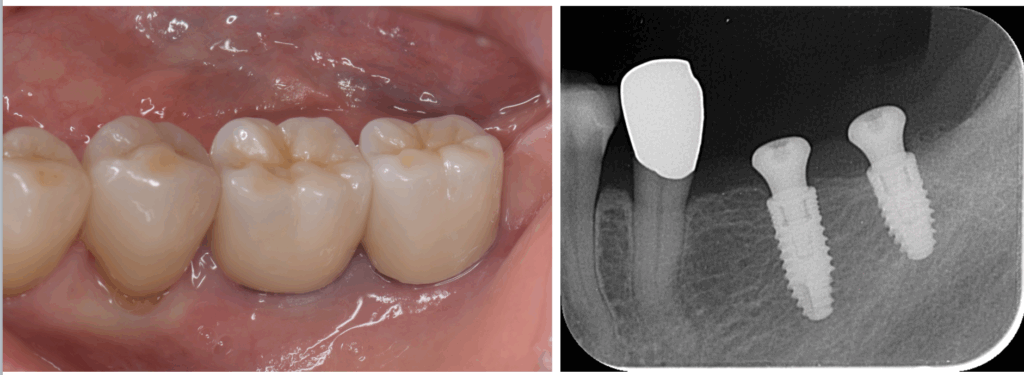

インプラント

インプラント治療は、他の歯に負担をかけず、自然な咬み心地と快適さを実現する唯一の方法です。